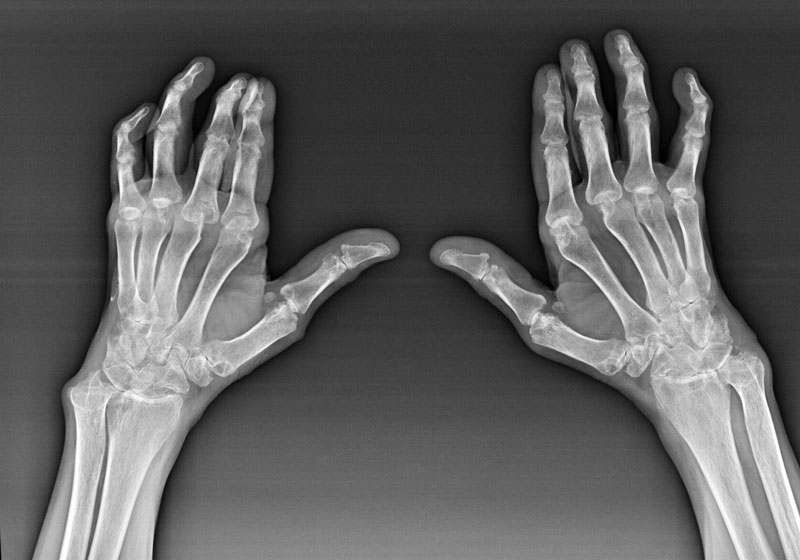

Обследование и диагностика

Для диагностики артроза кисти необходимо обратиться к врачу. Квалифицированный специалист определит наличие заболевания на основе жалоб пациента, соберет анамнез и проведет визуальный осмотр кистей.

Для подтверждения диагноза могут быть назначены следующие анализы и диагностические процедуры:

- клинический и биохимический анализы крови;

- анализ мочи;

- магнитно-резонансная томография;

- ультразвуковое исследование;

- рентгенография;

- артроскопия;

- пункция (при необходимости).

Эти исследования помогут отличить артроз от других ревматологических заболеваний, таких как артроз запястья или артроз лучезапястного сустава.